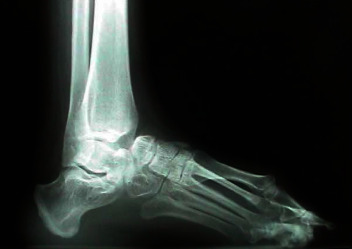

在这篇综述论文中,我们将介绍以下三种常见拇外翻的病因、表现、诊断和治疗方法:足背外翻、足尾外翻和足外翻(HV)。拇外翻是常见的病症,会出现在不同的诊所,因此医疗人员必须对这些病症有基本的了解,才能为患者提供最佳的治疗。许多拇外翻形成的原因多种多样,因此医疗服务提供者可以在需要手术干预之前对其进行处理。本综述旨在引起人们对这些常见拇外翻表现的关注,并扩大对这些表现的认识,以便在早期将发病率降至最低。本综述提供的信息将使初级保健医生和亚专科医生掌握准确诊断和最佳处理这些下肢骨性畸形的知识。

In this review paper, we present the common etiology, presentation, diagnosis, and management of the following three common bunion formations: dorsal bunion, tailor's bunion, and hallux valgus (HV). Bunions are common pathologies that present to a variety of clinics, so it is important for providers to have a base understanding of these in order to provide the best care to patients. Many of these bunion formations have a variety of causes which allow providers to manage them before surgical intervention is required. The aim of this review paper is to bring attention and expanded insight on these common bunion presentations in order to minimize morbidity early on. The information provided in this review will allow both primary care and subspecialty physicians with the knowledge to accurately diagnose and optimally manage these bony deformities of the lower extremity.